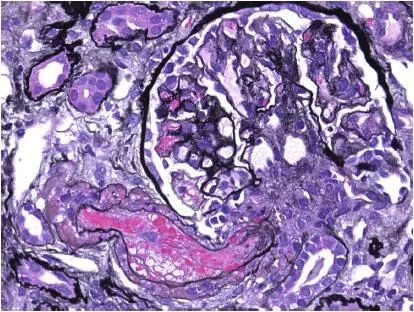

CNI肾毒性导致的血管收缩无形态学变化。急性CNI肾毒性特征包括:近端肾小管上皮细胞空泡化,大小一致;血管损伤,平滑肌细胞丢失;肌细胞胞浆空泡化;细胞坏死或凋亡退化。肌细胞损伤最终发展为局灶性结节性玻璃样变和透明样变,可延伸至小动脉和动脉血管壁整个中层。CNI肾毒性还可引起血栓性微血管病变(TMA),主要累及小动脉和肾小球毛细血管袢。慢性CNI毒性特征为:条状间质纤维化,肾小管萎缩。

图1 CNI肾毒性TMA,小动脉(Jones 银染)